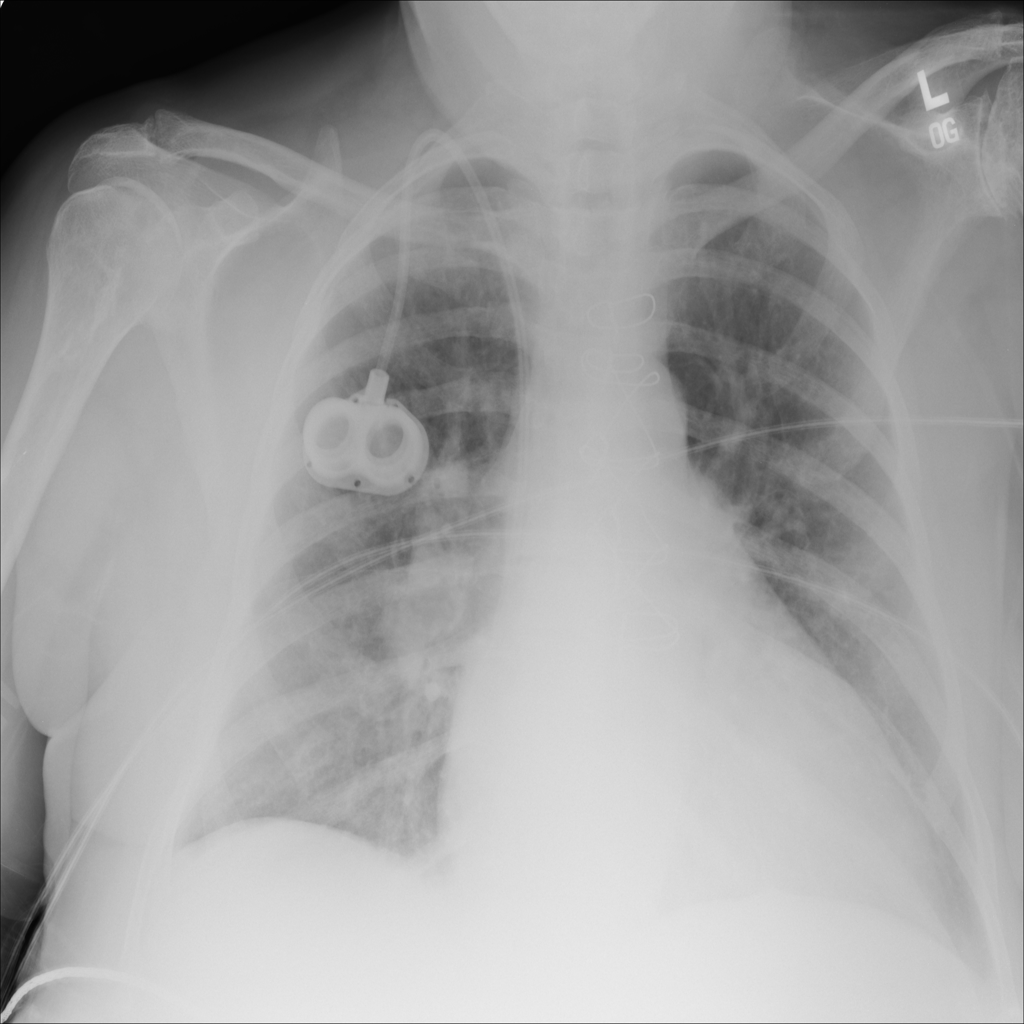

PAT-3384 · IMG-000Cardiomegaly

PAT-3384 · IMG-000

AP